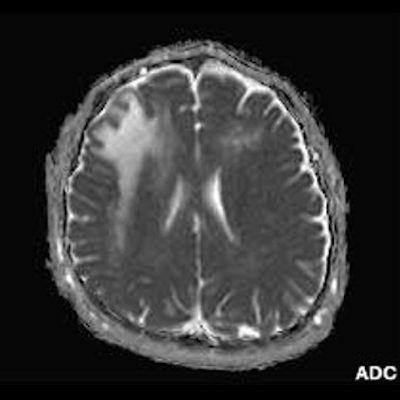

2. B) Aksiyel diffüzyon ağırlıklı serilerde bilateral sağda belirgin frontoparietal subkortikal ve derin periventriküler beyaz cevherde periferal DAG hiperintens ADC hipointens, hafif diffüzyon kısıtlaması (oklar) eşlik etmektedir. IVKM sonrası kesitlerde tarifli alanlarda belirgin kontrast tutulumu (oklar) izlenmedi.

3. Kontrastlı incelemelerde genellikle kontrast tutulumu izlenmez. Diffüzyon görüntülemede özellikle lezyonun ilerleyen periferik alanlarında yamalar halinde diffüzyon kısıtlılığı izlenir. MR spektroskopide NAA azalması, laktat varlığı ve artmış kolin ve lipid düzeyleri görülür. MR perfüzyonda ise lezyonların ilerleyen kenarında perfüzyon artışı saptanabilir.